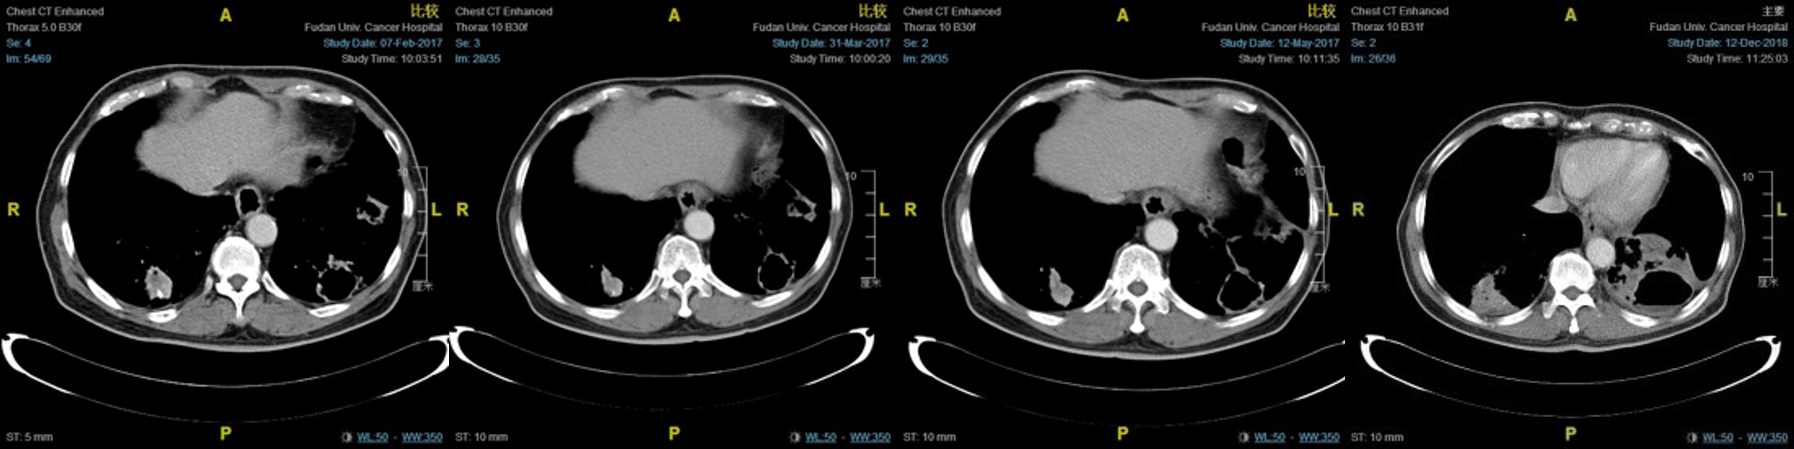

二线治疗:入组nivolumab对比多西他赛治疗既往接受过治疗的晚期或转移性非小细胞肺癌的随机、III期临床研究,随机入组nivolumab组,2016.06.06~2018.12.14给予nivolumab 234mg静脉滴注(体重78kg),q2w,每2个月进行疗效评价。

图1:治疗前(2016.05.20)胸部CT图像

图2:4次nivolumab治疗后(2016.08.29)胸部CT图像

图3:治疗10周期后(2016.12.29)胸部CT图像

图4:后续治疗的CT比较(至2018.12.12)

疗效评估:缓慢增大的SD

结合本例患者,这是一位老年男性,既往有吸烟史,ECOG1分,诊断为右肺腺癌术后两肺转移,EGFR、ALK野生型。一线接受4个周期培美曲塞联合卡铂4个周期,疗效评价SD,培美曲塞维持治疗1年后疾病进展。二线参加Checkmate-078临床研究,随机入组nivolumab组,接受3年的nivolumab 3mg/kg,q2w治疗,疗效评价为SD,病情发展是极为缓慢增长的趋势,在CT中我们可以明显看到空洞在缓慢增大。即使退出临床试验后该患者仍继续使用nivolumab治疗至今,二线的PFS已经超过3年。该患者生活质量极高,在整个治疗过程中未出现与免疫相关的不良反应。因此在该病例中,我们得出以下结论:1、年龄不是使用PD-1的影响因素,该患者为78岁高龄,使用纳武利尤单抗单药治疗3年余,生活如常人。2、SD依然能从纳武利尤单抗治疗中获得长期的生存获益,即使有缓慢增大趋势,但只要患者PS评分无显著下降,依然可以继续使用免疫治疗。3、活得长,活得好才是硬道理,Checkmate-017和-057,Checkmate-078研究结果告诉我们,纳武利尤单抗对比标准化疗,5年生存率显著高于化疗,并且不良反应远远低于化疗,不仅是各大指南的I类推荐,更是真正为中国肺癌患者提供了一种全新的治疗手段,造福于中国患者。